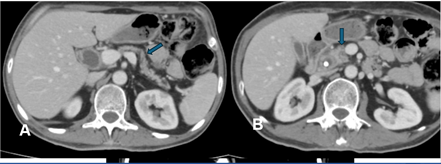

Endoscopic ultrasound (EUS) and fine needle aspiration (FNA) were performed, which showed benign ductal cells and some histiocytes. IgG4 levels were checked to rule out autoimmune pancreatitis, which was elevated at 502.6 mg/dL. The patient was started on prednisone 40 mg, and a follow-up CT scan after six weeks showed complete resolution of the pancreatic mass (Figure 2).

Figure 2: Follow up CT abdomen with contrast shows interval normal appearance of pancreas with clefts (blue arrow Figure 2A) and no mass at pancreatic head (blue arrow Figure 2B).